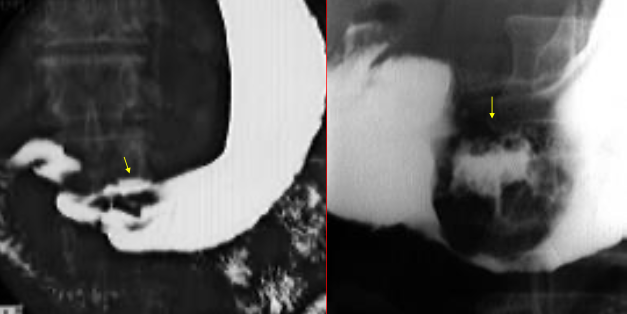

Neoplasm malign gastric ulcerant

Neoplasm malign gastric ulcero-vegetant